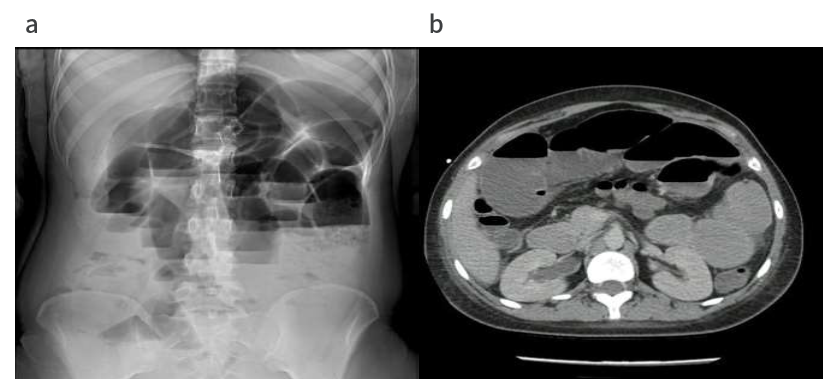

腹部X线平片显示小肠袢扩张伴气液面(图a),腹部CT

扫描显示轻度腹水,小肠袢扩张,肠壁增厚,右侧输尿管积水(图b)。